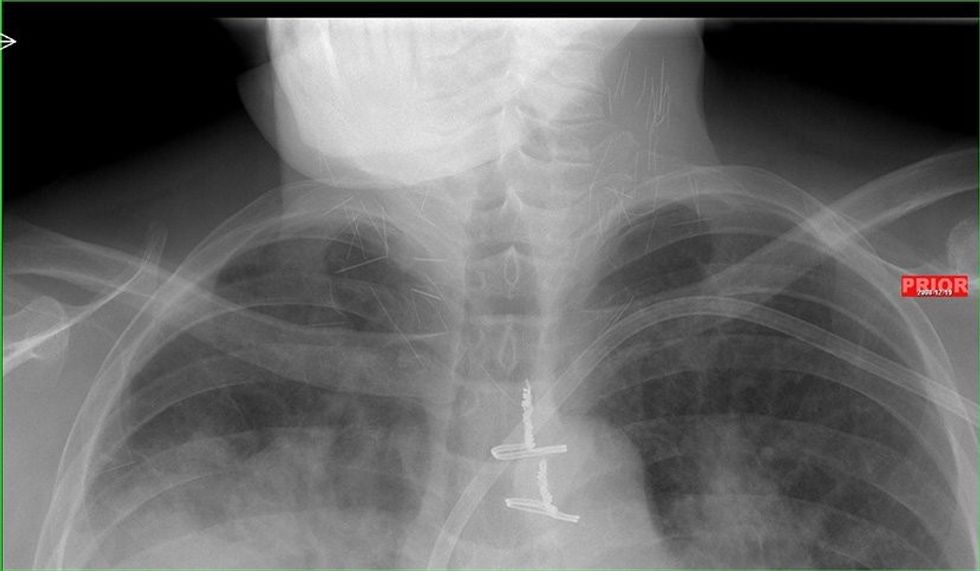

Pacienti i cili për një kohë të gjatë kishte qenë i varur nga heroina ka bërë një fotografim me rreze x, i cili ka zbuluar një të vërtetë të tmerrshme.

Fotografia e rëntgenit me rreze x ka nxjerr në pah dhjetëra gjilpëra të thyera në qafën e tij, ndërsa pas rekonstruimit të fotografisë në versionin 3D nga radiologët, është konstatuar se vërtetë bëhet fjalë për dhjetëra gjilpëra.

Mjekët besojnë se ky narkoman i cili sipas të gjitha gjasave nuk kishte pasur ku të shpohet në duar, dhe kështu kishte injektuar heroinën në venat e qafës.

Injektimi i heroinës në qafë mund ta lë pavetëdije narkomanin për disa sekonda, ku si pasojë gjilpëra mund të thyhet dhe një pjesë e saj të mbetet në qafën e tij.